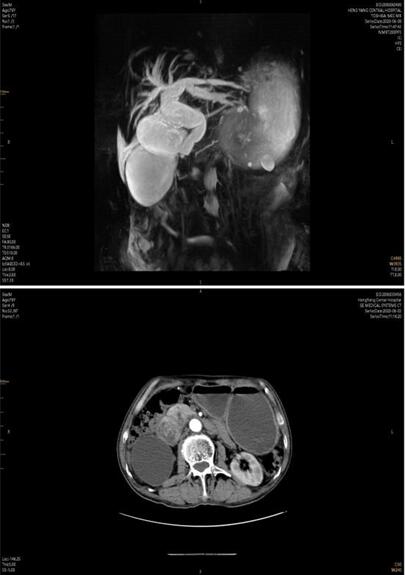

患者家屬經(jīng)多方打聽,赴我院胃腸外科會診。譚曙光主任及賀賽奇副主任閱外院腹部CT片,考慮十二指腸惡性腫瘤合并梗阻可能性大,唯有手術(shù)治療方為解決患者病癥最好方式??紤]患者高齡,全身營養(yǎng)狀況差,脫水及貧血嚴(yán)重,予積極補(bǔ)液、維持水電解質(zhì)平衡、腸外營養(yǎng)支持及輸血治療同時,完善術(shù)前相關(guān)輔助檢查。上腹部增強(qiáng)MRI+MRCP檢查提示:十二指腸水平段腫瘤,侵犯膽管下段、胰頭、橫結(jié)腸系膜,并周圍多發(fā)淋巴結(jié)腫大。十二指腸鏡下活檢病理:十二指腸粘膜慢性炎。